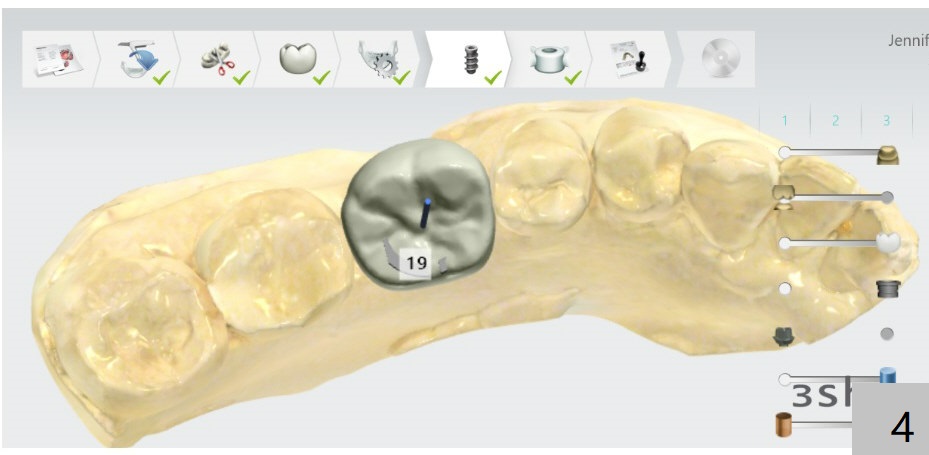

Buccal Plate Collapse: Lingual Placement

Return to Lower Molar Immediate Implant, Trajectory II